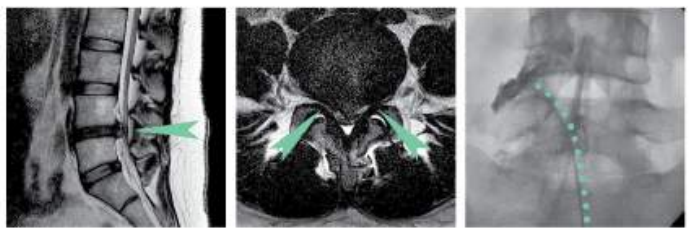

▲20~30대 허리디스크 주사 치료

갑자기 느껴진 엉덩이와 다리 저림 증상으로 내원하신 환자 분입니다. 평소 앉아있을 때도 요통이 있었지만 조금 불편한 정도라 생각하고 방치하시다가 급성 허리 통증으로 이어진 경우입니다. 내원 당시 걷기 힘든 정도의 통증을 호소하셨습니다.

제대로 움직이기 힘든 운동마비를 동반한 디스크는 신경학적 상태를 확인하는 것이 중요합니다. 당일 분당 콕통증의학과 허리디스크 입원실 입원 후 MRI 촬영을 진행하였으며, 그 결과 요추부 4번, 5번 우측 디스크 탈출증과 협착증 진단을 내렸습니다.

CI 치료에는 효과가 미미하여 PEN 시술 후 많이 회복하셨고, 치료 3개월 차에는 허리통증 (감각)과 운동 마비 모두 크게 호전되어 병원 측으로 감사인사를 전해오셨습니다.